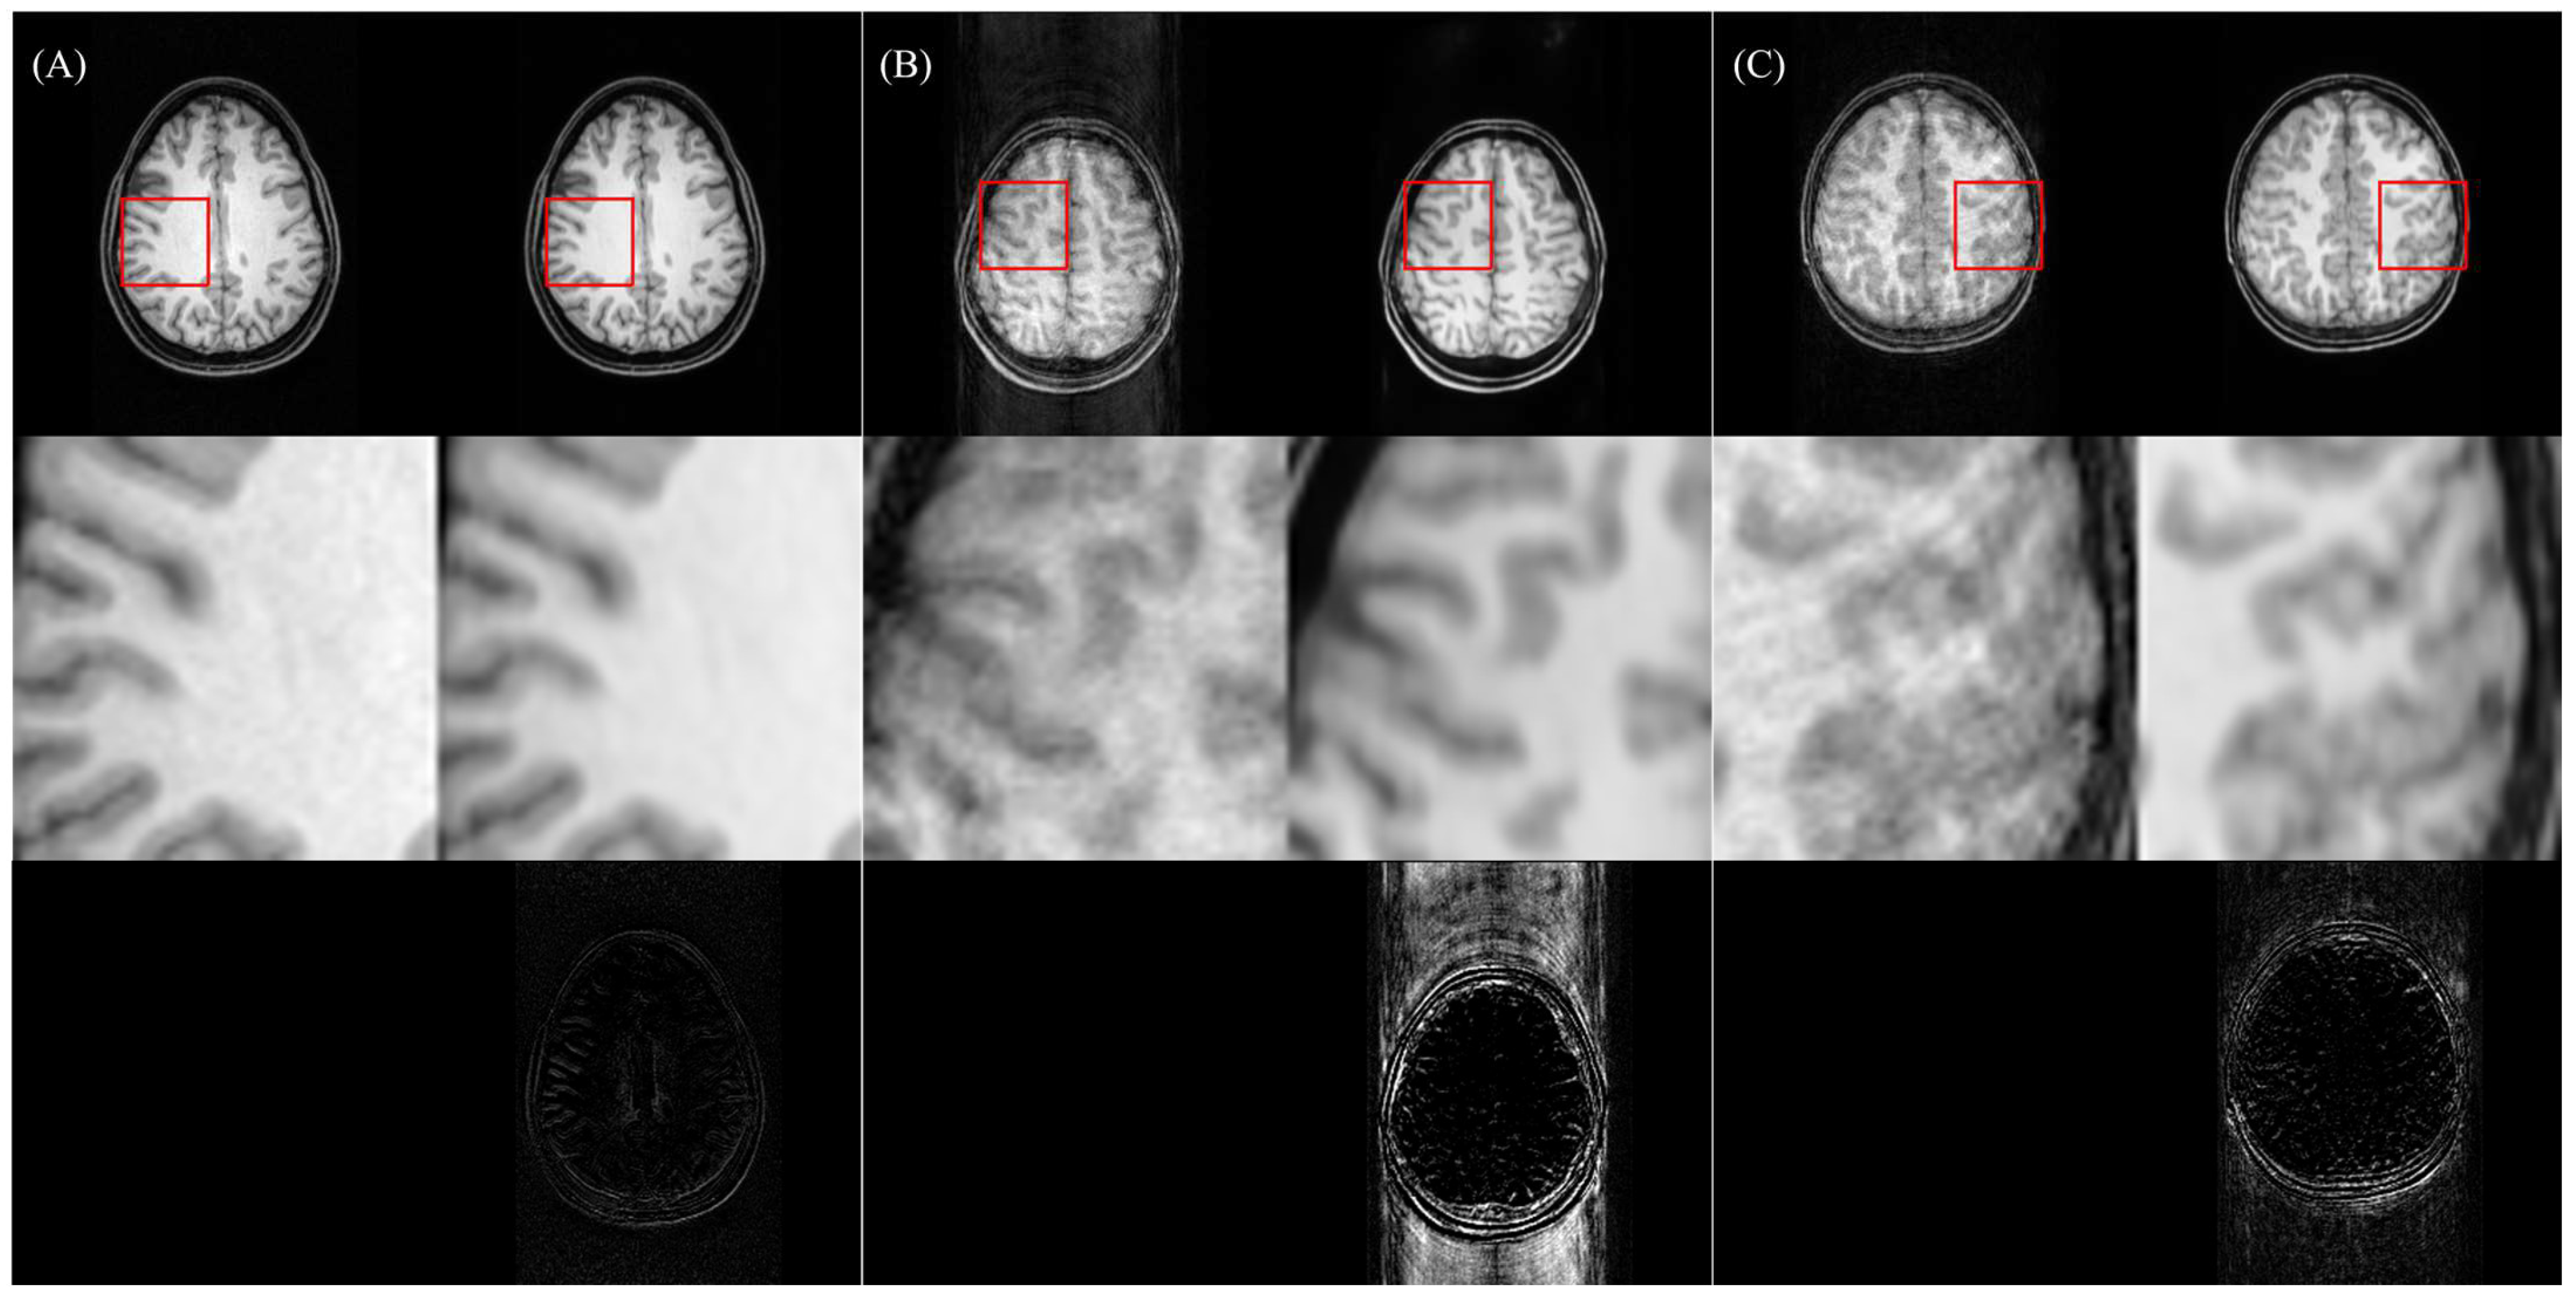

4.2. Effects on Artifact-Free Images